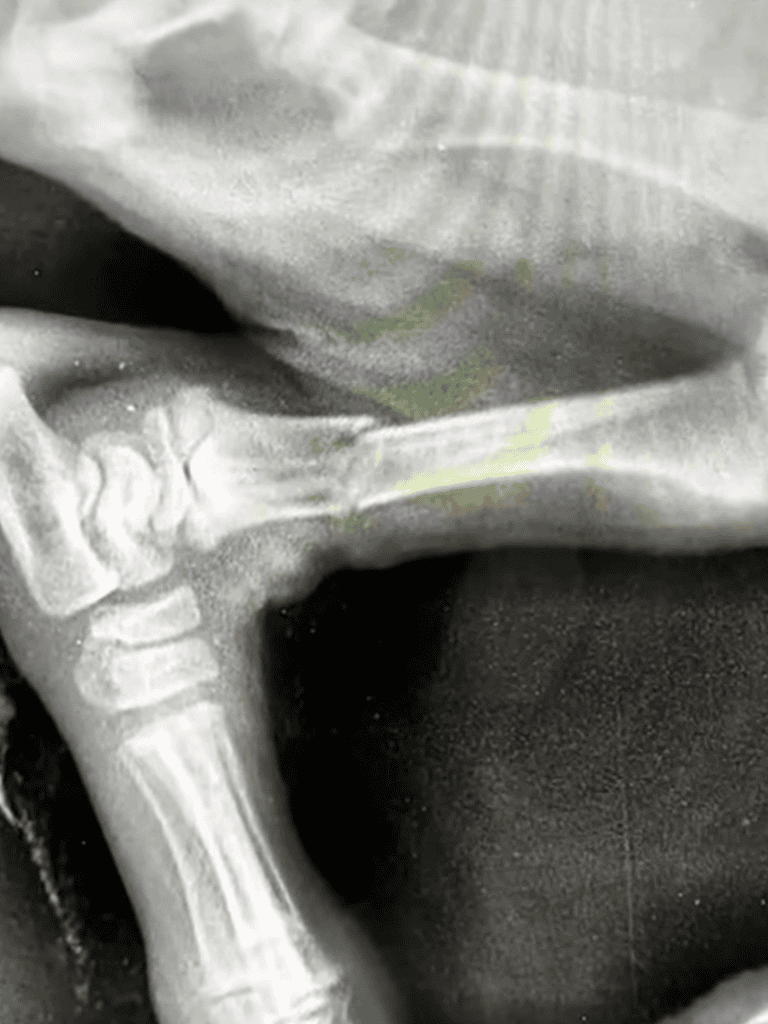

Nana’s Injuries

Nana’s front legs were twisted from past confinement, and one back leg was broken, suggesting a violent encounter.

Her young body bore the marks of suffering.

Nana’s body wasn’t ready yet, but surgery was next.